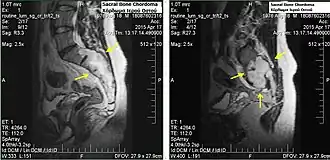

Sacral bone chordoma

Chordomas can arise from bone in the skull base and anywhere along the spine. The two most common locations are cranially at the clivus and in the sacrum at the bottom of the spine.[2] Very rarely, chordomas present outside of the skull base or spine; these are called extra axial chordomas.[3]